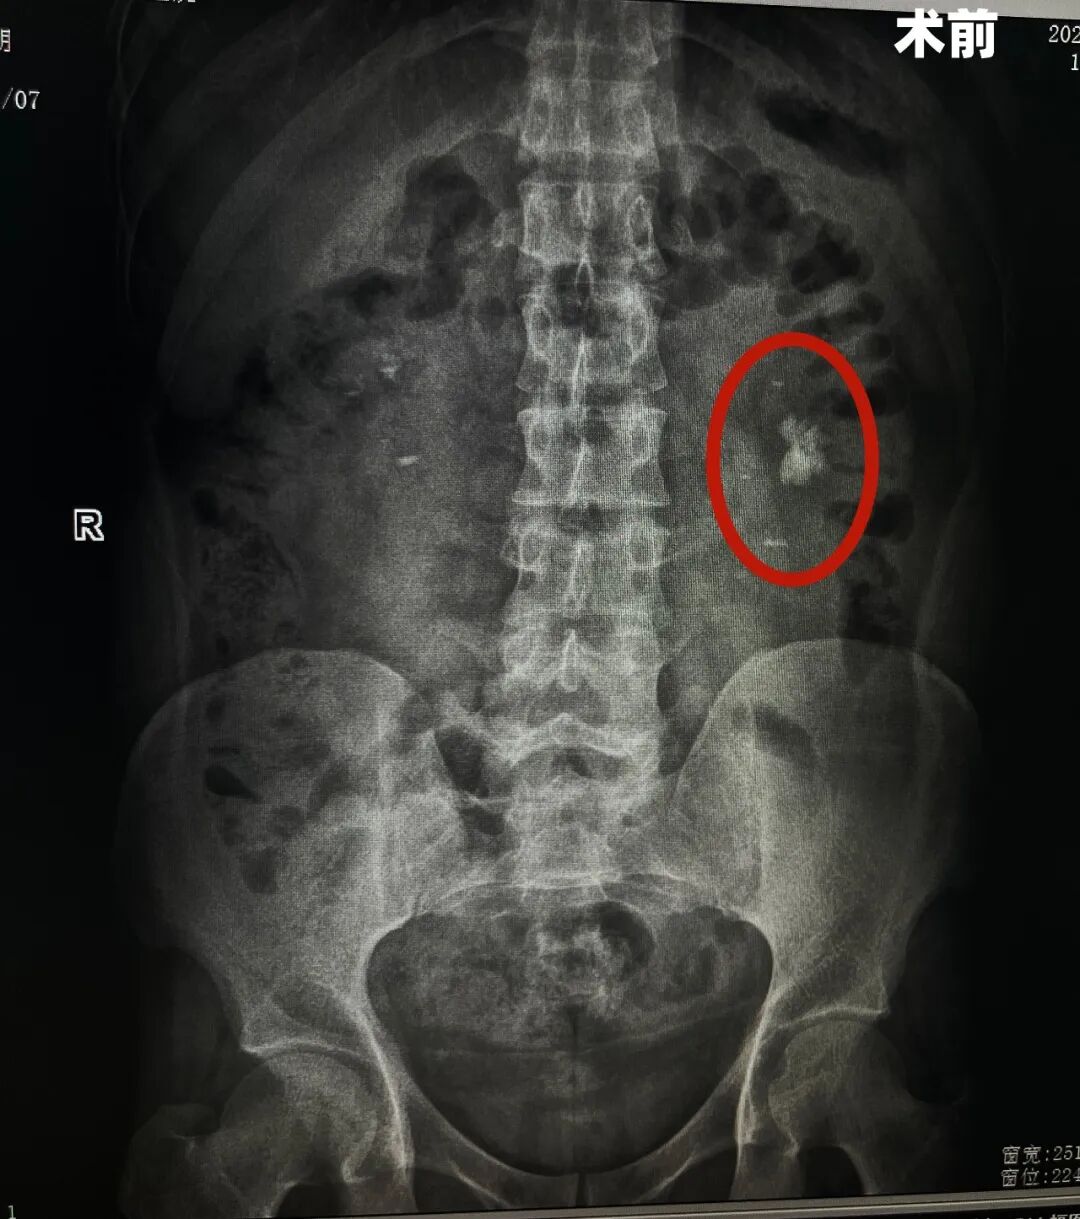

术前

图片

据了解,该患者因“左侧腰部间断性疼痛2月”来院就诊。经详细检查,诊断为左肾结石伴有积水和感染,且结石体积较大,已对肾功能造成潜在威胁,手术指征明确。同时,患者还合并双侧肾囊肿、髓质海绵肾及乙型病毒性肝炎,多重基础疾病为手术治疗带来了诸多挑战。

髓质海绵肾是一种先天性肾脏发育异常,患者肾集合管呈囊状扩张,易形成结石并反复感染,手术操作空间受限、出血风险较高;而乙型病毒性肝炎则对术中感染控制及术后康复管理提出了更高要求。面对复杂病情,泌尿外科团队高度重视,术前组织多学科会诊,围绕手术方式、围手术期感染防控、出血风险控制及肝功能保护等关键环节进行了充分评估与周密准备。